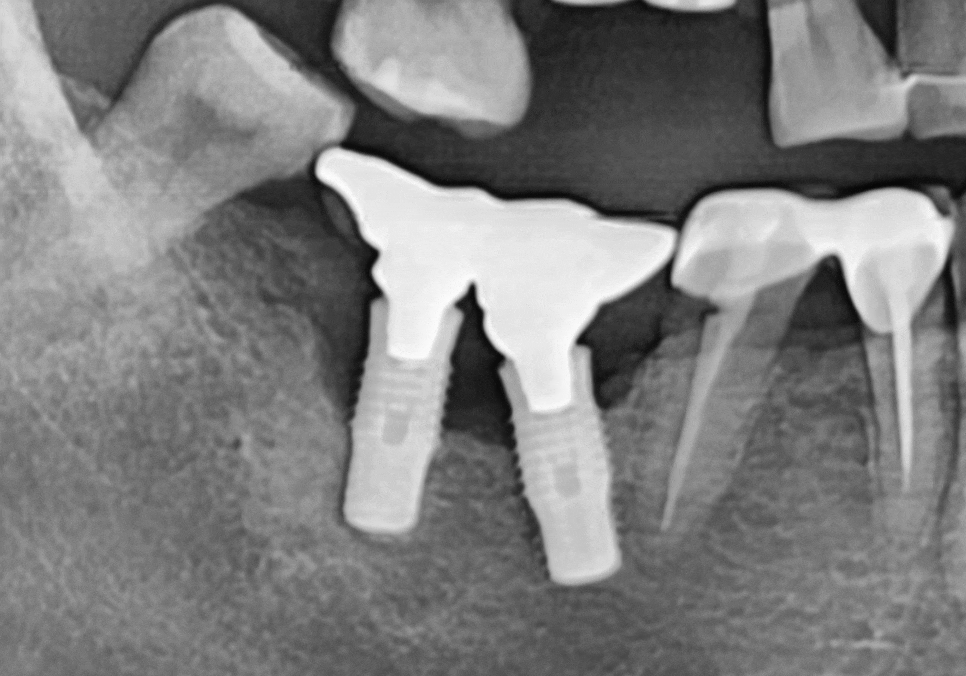

특히 CT로 분석해 보니 임플란트를

양옆에서 꽉 잡아줘야 할 뼈 중

한쪽 면이 염증으로 완전히 소실되어 있었죠.

우선 염증의 원인인 사랑니와

이미 뼈가 녹아버린 임플란트들은

발치가 불가피했습니다.

여기서 저는 환자분의 비용

부담을 줄여드리기 위해

양 끝에 2개의 임플란트 기둥만 튼튼하게 심고,

그 사이를 보철로 연결하는 방식을

제안해 드렸습니다.

치아를 3개 뽑았다고 해서

임플란트를 꼭 3개 다 심어야 하는 건 아니거든요~

불필요한 뼈이식도 막기 위해

CT를 꼼꼼히 분석했고,

꼭 필요한 부분(#47)에만 뼈이식을

동반해 안전하게 식립을 마쳤습니다.

260105